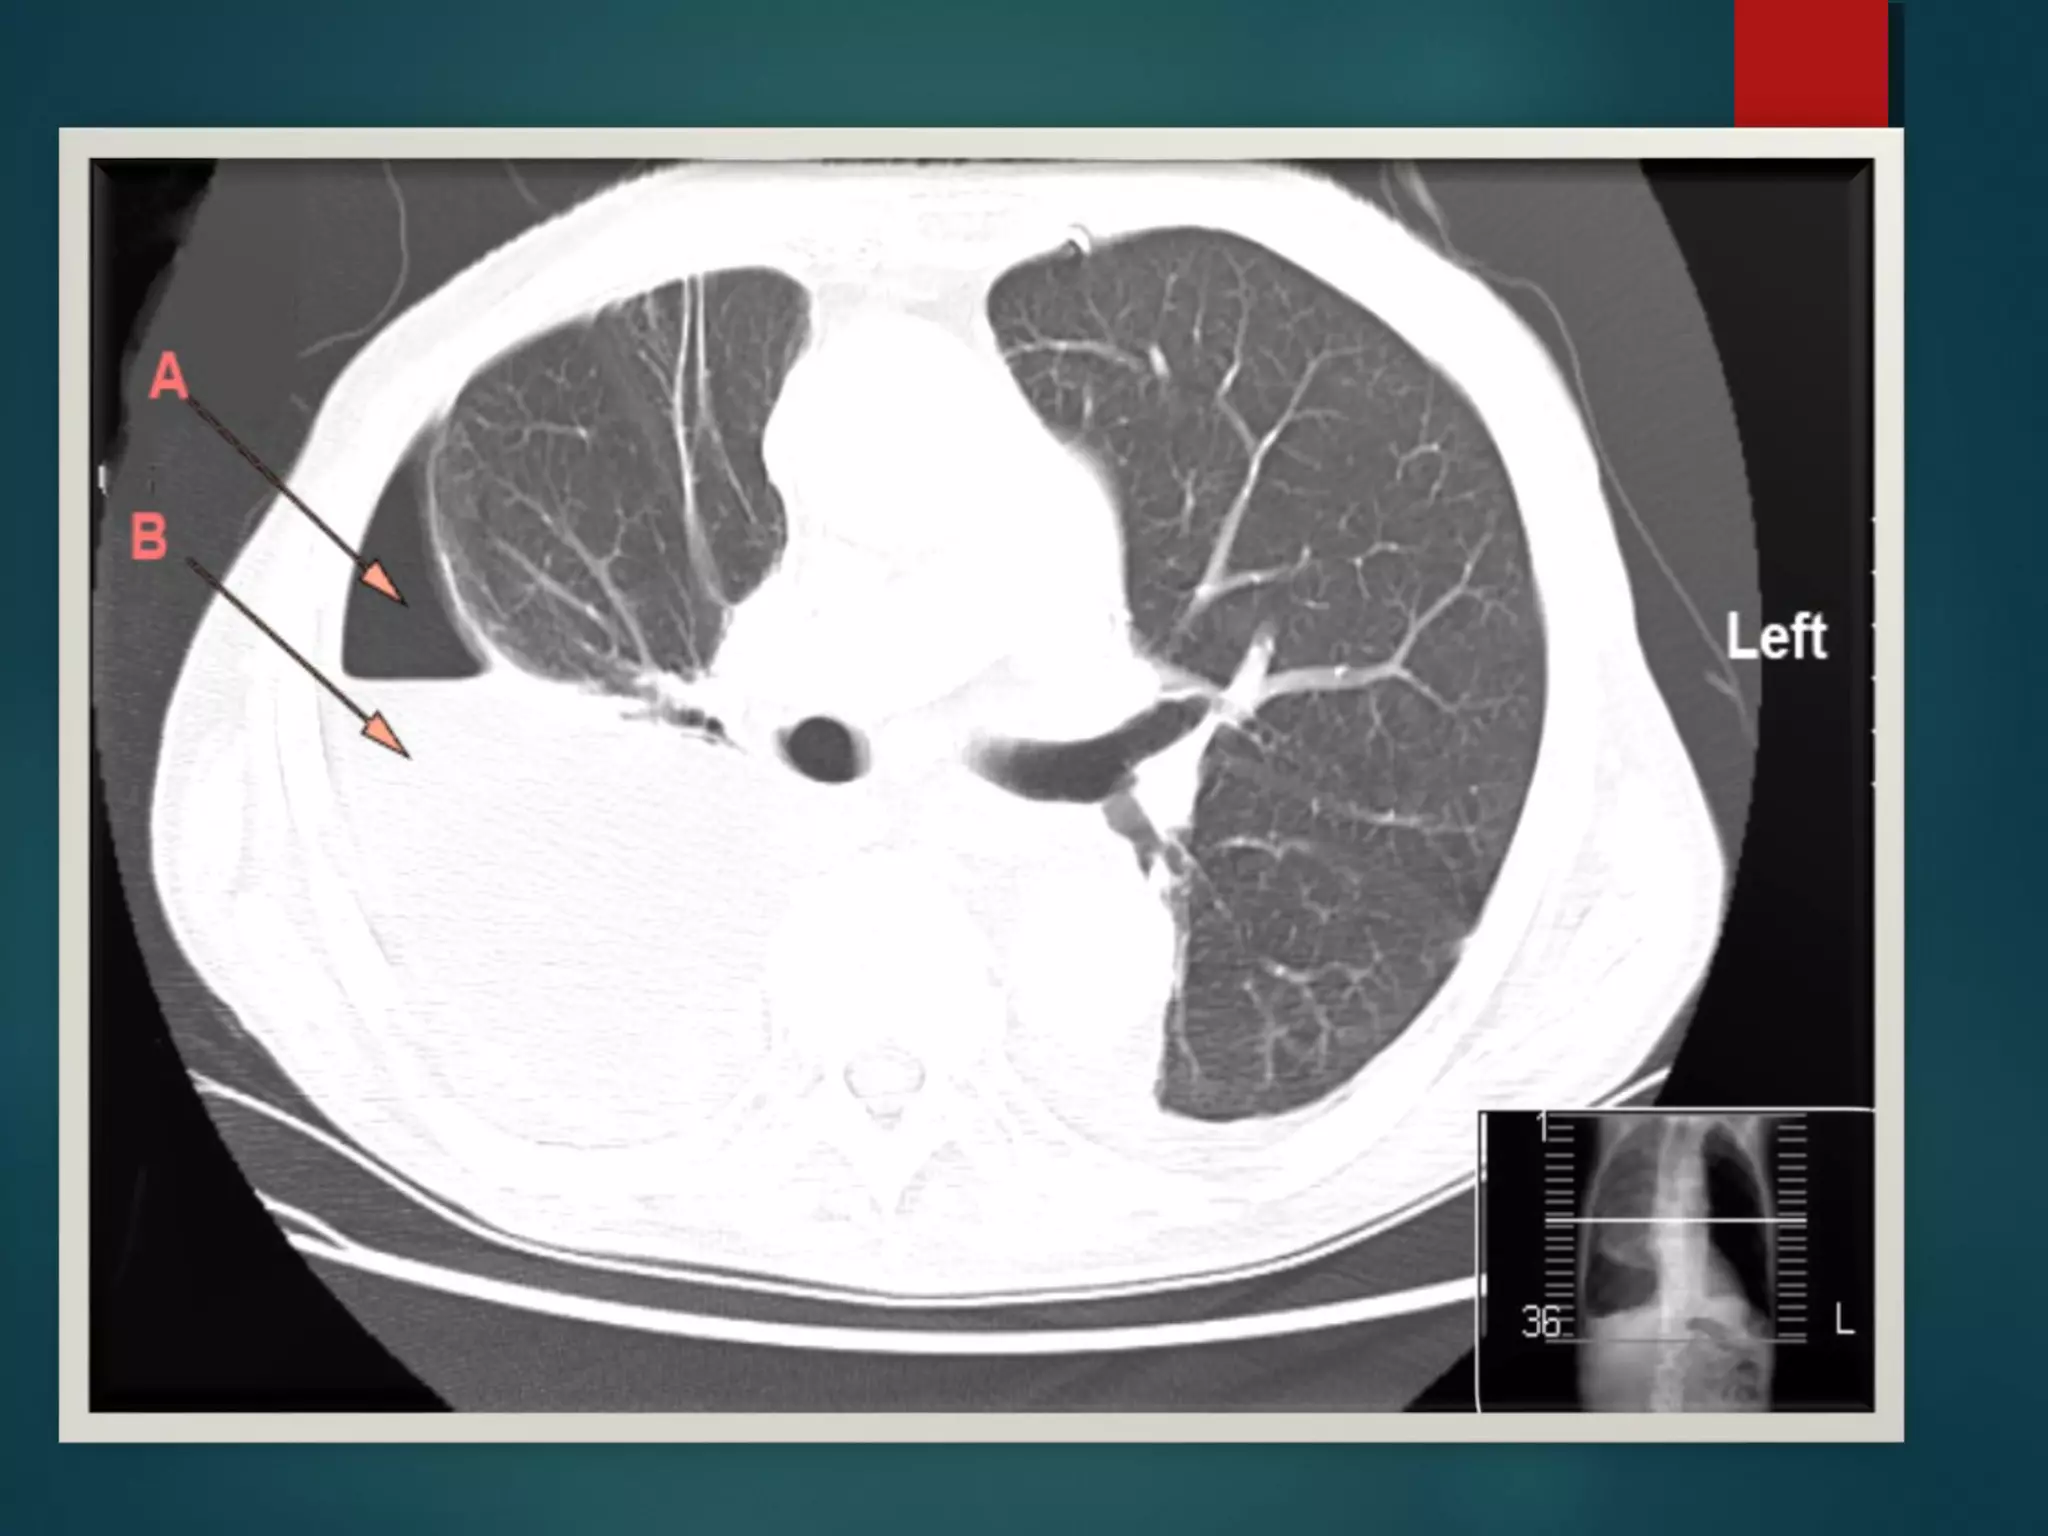

Empyema Ct scan

empyema